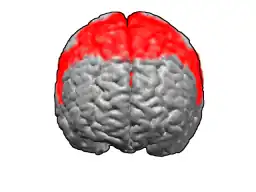

Цитоархитектоническое поле Бродмана 6

Цитоархитектоническое поле Бродмана 6 — область коры больших полушарий головного мозга, которая располагается в лобной доле в передних отделах прецентральной и задних отделах верхней и средней лобных извилин. При поражении у человека возникает кинетическая (син. эфферентная, премоторная) апраксия.

В 1909 году немецкий невролог Корбиниан Бродманн опубликовал[1] карты цитоархитектонических полей коры больших полушарий головного мозга. 6-е поле располагается в передних отделах прецентральной извилины и задних отделах верхней и средней лобной извилин.